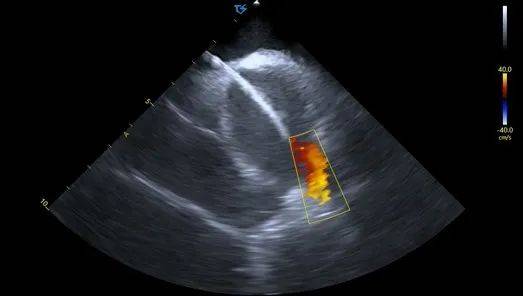

血流模式确认左上肺静脉

血流模式确认左下肺静脉